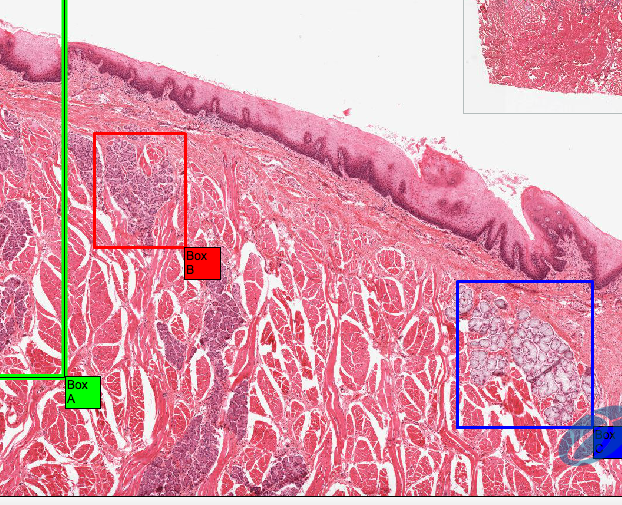

This is taken from the lip. What is the arrow pointing to?

The upper surface of the lip consists of hairy skin and the red arrow is pointing to a hair follicle

For the lips give

a) Mucosa

b) Fibers in connective tissue

c) Structures in the deep layers

a) Stratified squamous non-keratinising epithelium

b) sub-mucosa of collagen and elastin with small vessels to keep them moist

c) deep layers of skeletal muscle

What is the arrow pointing to?

The abrupt transition between stratified squamous keratinising epithelium and non-keratinising epithelium

On the inner lip, what opens on to the surface instead of hair follicles?

Sebaceous glands (Fordyce’s spots)